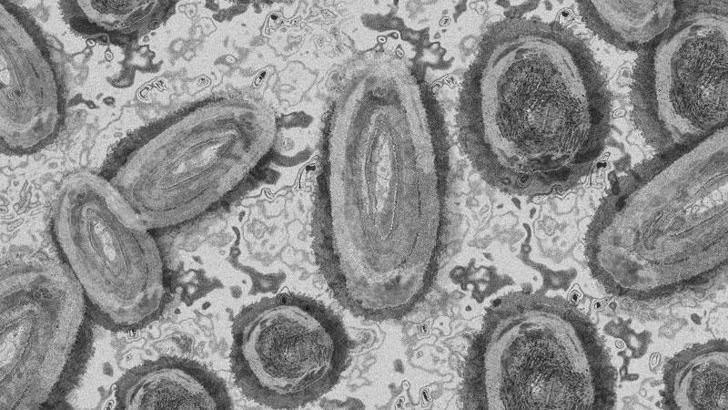

Avrupa Birliği’nin yürütme organı AB Komisyonu, 2023 ve 2024 boyunca 2 milyon doza kadar maymun çiçeği aşısı temini için Bavarian Nordic şirketi ile sözleşme imzaladığını açıkladı. Aşıların ilk tesliminin 2023’ün ikinci yarısında yapılacağı belirtilerek maymun çiçeği hastalığının Avrupa’da bir salgına dönüşmemesi için önlem alındığı vurgulandı.

Dünya Sağlık Örgütü’nün bugün yayınladığı küresel rapora göre, Ocak 2022’den itibaren 110 ülkeden laboratuvar testli 80 bin 221 maymun çiçeği vakası rapor edildi. Hastalıktan 52 kişi yaşamını kaybetti. DSÖ açıklamasında “13 Mayıs 2022'den bu yana vakaların yüksek bir oranı, daha önce belgelenmiş maymun çiçeği bulaşmasının olmadığı ülkelerden bildirilmiştir” ifadelerini kullandı.

DSÖ, maymun çiçeği salgının küresel riskini ‘ORTA’ olarak değerlendirdi ancak Amerika kıtalarındaki riskin ‘YÜKSEK’ olduğunu vurguladı. Afrika Bölgesi, Doğu Akdeniz Bölgesi, Avrupa Bölgesi ve Güneydoğu Asya Bölgesi'nde riskin ‘ORTA’ olduğu belirtildi. DSÖ, Batı Pasifik Bölgesi'ndeki riski ise ‘DÜŞÜK’ olarak belirledi.